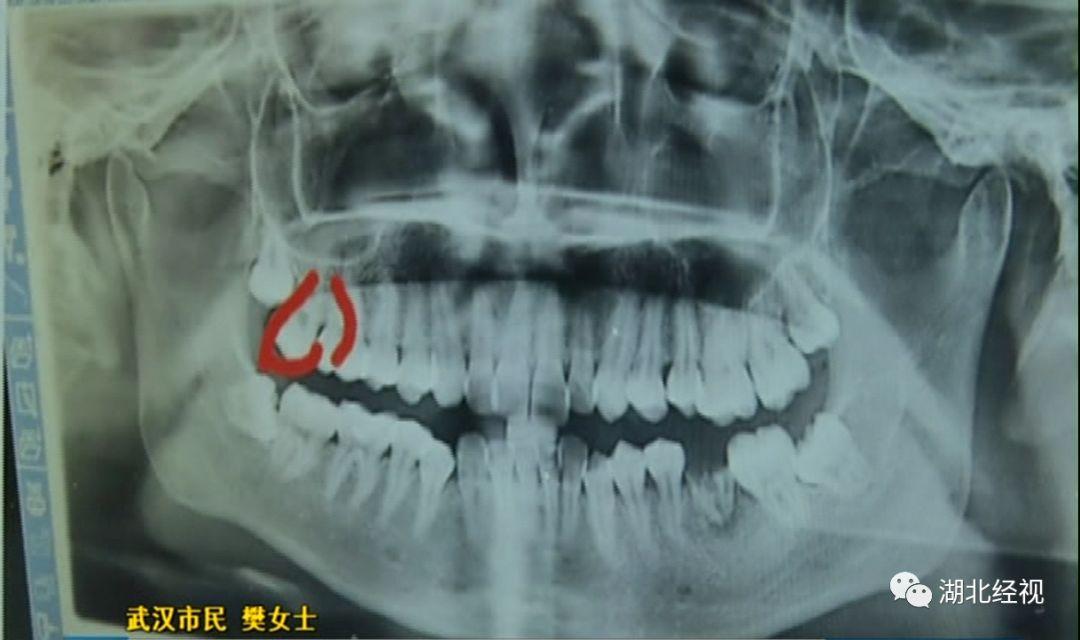

拔智齒旁邊的好牙沒了

樊女士說,拔牙時上了麻醉,嘴巴里都是麻的也沒有感覺。但回家一個星期后照鏡子,突然發(fā)現(xiàn)自己的一顆好牙沒有了,一顆好牙齒被這樣被拔掉了。

原本是準(zhǔn)備拔掉多余的牙齒,但醫(yī)生卻意外拔掉了一顆好牙,這讓樊女士痛心不已。

記者陪同樊女士找到了武漢第一口腔醫(yī)院,院方醫(yī)務(wù)部門對于錯拔樊女士好牙的投訴并不否認(rèn),并表示已對醫(yī)生進(jìn)行了批評。